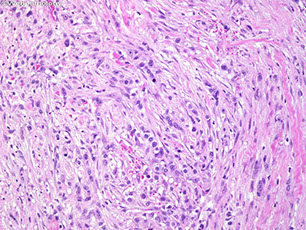

Deep Fibromatosis (Desmoid tumors)

Infiltrative, sometimes painful lesion of clonal fibroblasts in deep ST/muscle c irregular borders that frequently recur but don't met

- 2nd to 5th decades (esp head and neck if in kids) MC in shoulder (1/4), chest wall, thigh if outside abdomen

- 3 F > 1 M; usually as an abdominal wall mass

- not as common as superficial fibromatosis

- can be lethal 2/2 mass effects when in head and neck of kids

- may be familial and assoc c Gardner's syndrome

Micro: Bland long sweeping fascicles (usually that go all the way across the microscope field) c bipolar fibroblasts / myofibroblasts  c amphophilic cytoplasm that blends into surrounding collagen and have very open chromatin and large single prominent nucleolus

- has thick-walled, intermediate-sized BVs between fascicles, sometimes with perivascular edema

- cancer cells are bwt super thick fibrous bands (is more collagenous and less cellular than nodular fasciitis)

- regenerating muscle can form MNGC-oid cells

- few mits, no atypia

Cyto: bland individual/single spindle cells c long fusiform nuclei and metachromatic matrix material possibly in a fascicular pattern

IHC: (+) vimentin, SMA and CD117 (variable, can be a pitfall for GISTs!!!), nuclear B-catenin (sensitive but not specific; see genes below), ER-beta

- negative: keratin, S100, CD34, ALK, desmin, ER-alpha, PR, MUC4

Genes: Clonal, assoc c Wnt/B-catenin (APC-B catenin - Tcf) pathway, trisomies 8 and/or 20, APC inactivation

- APC binds B-catenin, in Wnt pathway, so inactivation of APC causes build-up of nuclear B-catenin (which causes a positive nuclear B-catenin stain; thus reactive scars and nod fasc has positive cytoplasmic B-catenin, not nuclear B-catenin like those seen in clonal fibromatosis)

- pts c FAP / Gardner syndrome c germline APC mutations on cr 5q are predisposed, and are intra-abdominal

- sporadic tumors are extra-abdominal and assoc c CTNNB1 mutation

Tx: Wide-margin excision (tends to recur)

- chemo/rads can be helpful

DDx: GISTs are more cellular, are located within the muscle layer, and have larger endothelial cells; Leiomyosarcoma have nuclear pleomorphism, more eosinophilic cytoplasm, and perpendicular fascicles

Desmoid fibromatosis with long sweeping fascicles

Desmoid fibromatosis with medium-sized BV